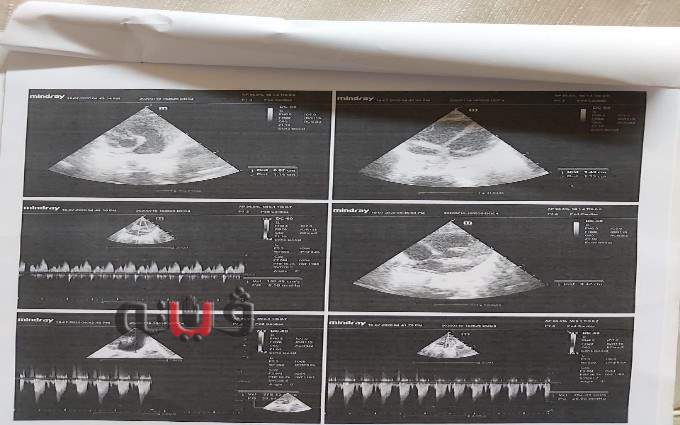

وأضاف والد الرضيع، تزوجت قبل ١٠ سنوات ونعيش فى قرية فرسيس مركز زفتي بمحافظة الغربية، واعمل سباك صحي حر، والعمل غير منتظم والدخل غير ثابت، وريان هو طفلي الثاني بعد إسماعيل وعمره ٦ سنوات، والطفلان عن طريق الحقن المجهري، وعقب ولادته وبالتحديد بعد يوم من الولادة سمعنا صوت غريب في صدره، وتوجهنا لطبيبة متخصصة في القلب والتي بدورها طلبت أشعة "الايكو" والتي اثبتت اصابته بضيق وانعكاس بشرايين القلب وبثقبين بالقلب احدهما بين الاذينين والآخر بين البطينين ولابد من تدخل جراحي وأوصت بعرضه علي اطباء استشاريين في جراحة القلب والذين أوصوا بنقله إلى مركز مجدى يعقوب للقلب بمدينة أسوان او مستشفي ابو الريش او اي مركز كبير لجراحات القلب للاطفال، وماديًا لا استطيع إلا المراكز الحكومية المجانية.